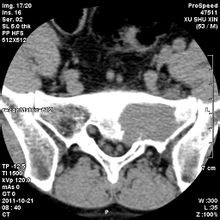

現(xiàn)年39歲的劉某,家住岱山。截止上個(gè)月,一場(chǎng)揮之不去的噩夢(mèng)時(shí)刻纏繞著她,令她寢食難安。骶骨腫瘤,就是這么一個(gè)簡(jiǎn)單的醫(yī)學(xué)名詞,卻給她帶來(lái)無(wú)盡的痛苦。

“手術(shù)成功,請(qǐng)靜等出院”,對(duì)于這句話,無(wú)法用言語(yǔ)來(lái)形容當(dāng)時(shí)劉某的心情,只知道嚴(yán)教授和劉副院長(zhǎng)的強(qiáng)強(qiáng)聯(lián)合成就了廣安醫(yī)院乃至全市的美談。舟山市首例骶骨腫瘤成功手術(shù),竟發(fā)生在一所民營(yíng)醫(yī)院,這似乎是一場(chǎng)偶然,卻似乎又是一種必然……

骶骨常見(jiàn)的良性腫瘤有骨母細(xì)胞瘤(成骨細(xì)胞瘤)、骨巨細(xì)胞瘤和動(dòng)脈瘤樣骨囊腫等,常見(jiàn)的骶骨惡性腫瘤有脊索瘤、軟骨肉瘤等。手術(shù)治療是多數(shù)骶骨腫瘤的首選方案,該區(qū)域手術(shù)時(shí)出血多且不易止血,曾被視為手術(shù)禁區(qū)。